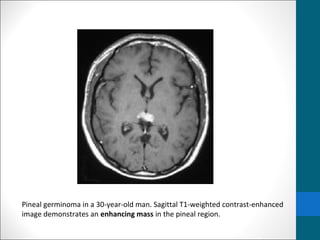

Pineal germinoma in a 30-year-old man. Sagittal T1-

weighted contrast-enhanced image demonstrates an

enhancing mass in the pineal region.

Pineal germinoma ina 30-year-old man. Sagittal T1- weighted contrast-enhanced image demonstrates an enhancing mass in the pineal region.